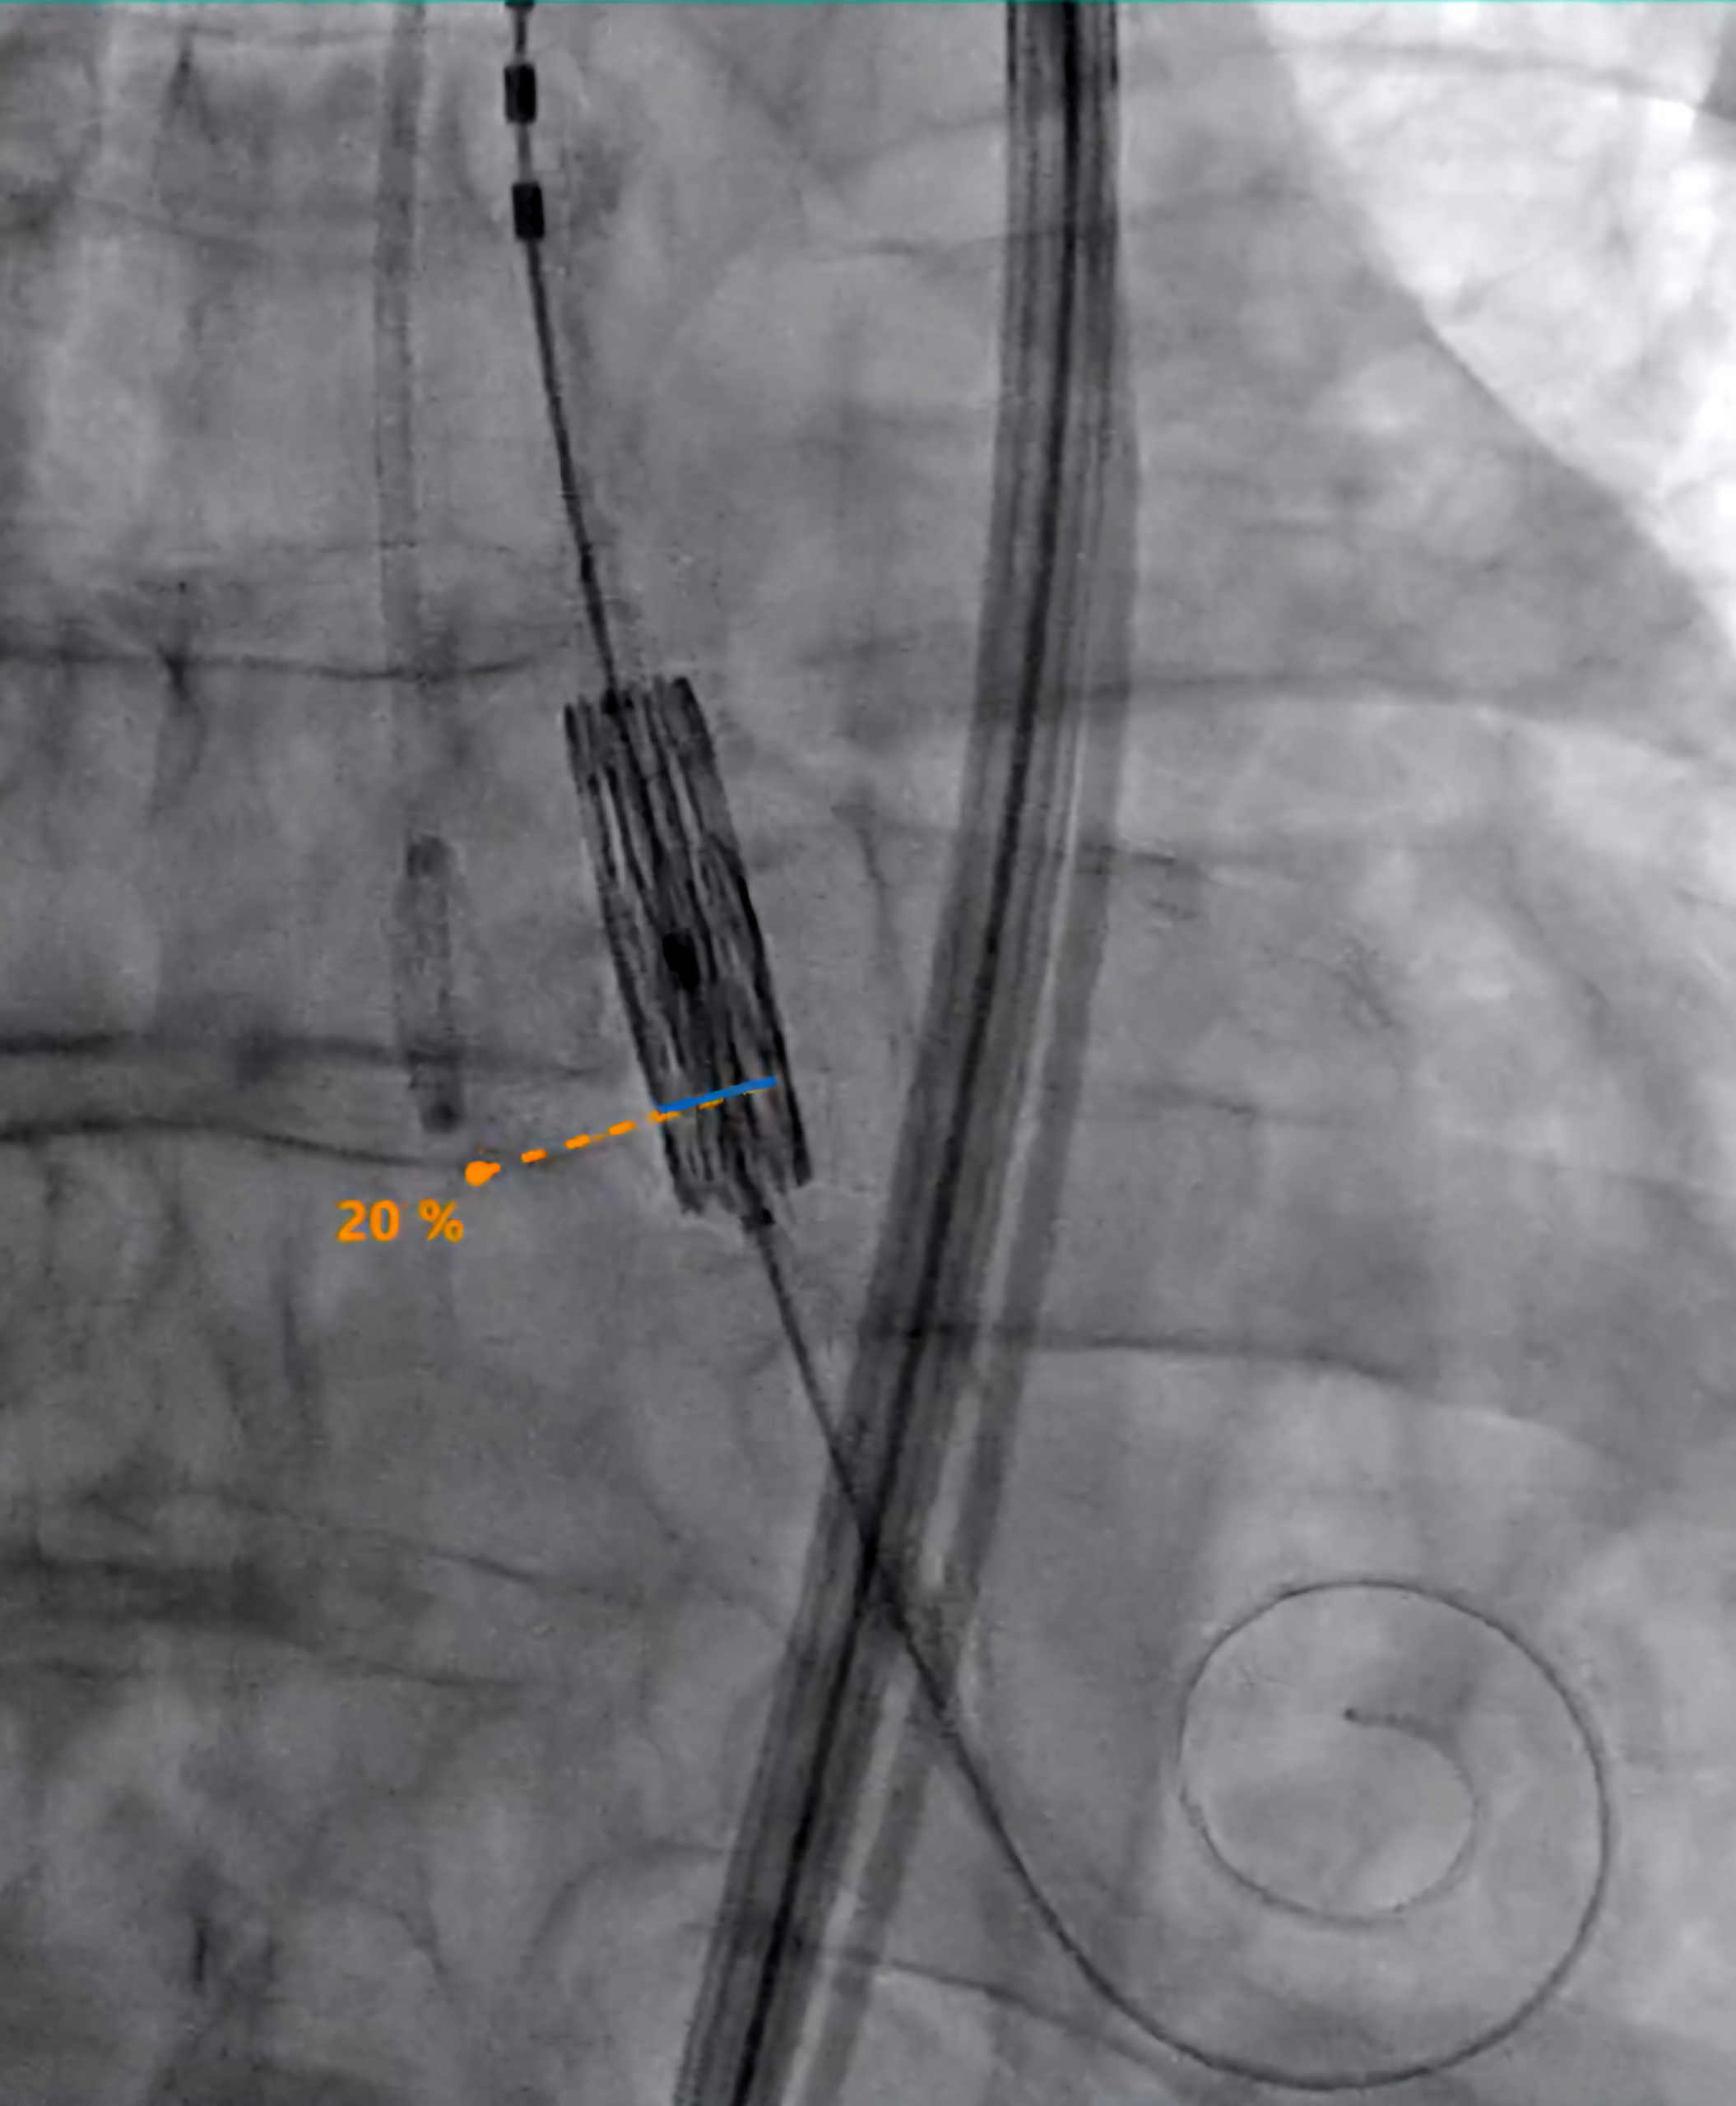

MITRA-PILOT combines advanced image guidance, AI, robotics, and the proprietary EPYGON biomimetic transcatheter mitral valve to autonomously deliver prosthetic mitral valve.

Epygon is the first “physiological” transcatheter mitral valve restoring the natural blood flow vortex in the left ventricle. It fosters recovery of ventricular function, especially in fragile patients with a seriously impaired cardiac condition.

By integrating AI guidance and robotic precision with biomimetic valve design, MITRA-PILOT aims to deliver a differentiated and physiologically optimized solution for mitral valve replacement.

Epygon makes it possible to generate blood flow closest to normal flow inside the left ventricle, avoiding in particular the stagnation of blood inside the ventricle. Furthermore, this asymmetrical valve, lower in height on the side where the left ventricle ejects, just under the aorta valve, optimizes the ejection function. It doesn’t impede the aortic valve, as with some other devices.